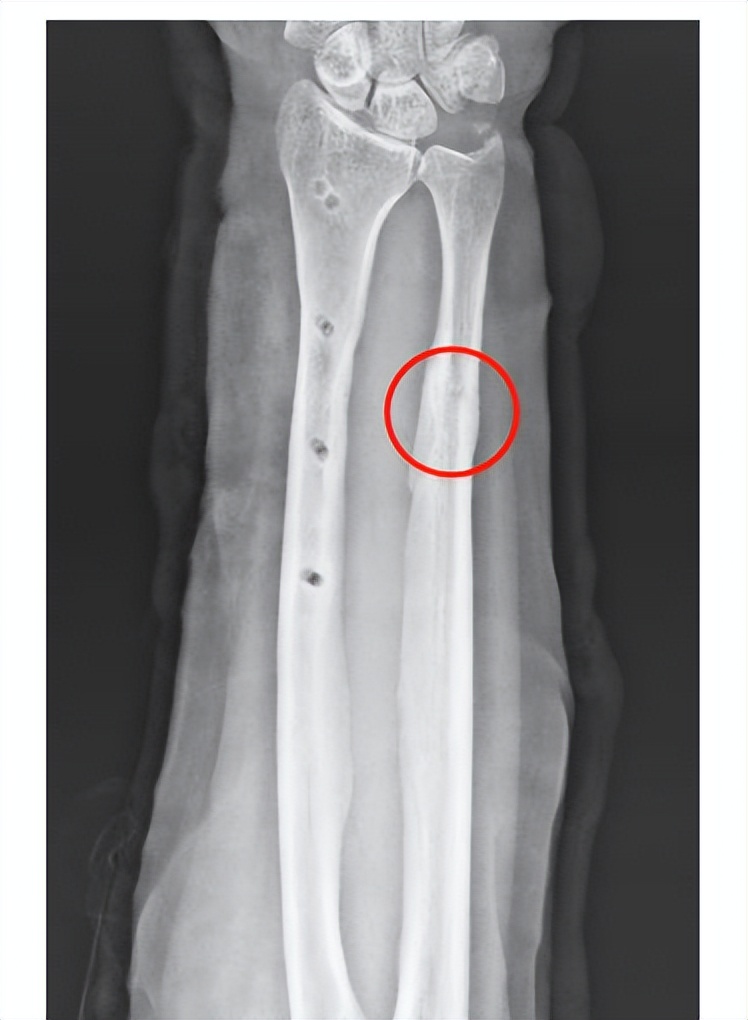

在术后6个月的时候,在病人的要求下,取出了钢板和弹性钉。病人最后一次来医院的时候,前臂的腕关节的背伸功能、掌曲功能以及前臂的旋转功能已经完全接近正常。骨不连完全愈合,这个愈合速度其实已经超出了传统植骨手术,而且没有给病人增加额外的创伤,病人对这种治疗方式非常满意。

(生长因子注射术后6个月去除内置物)